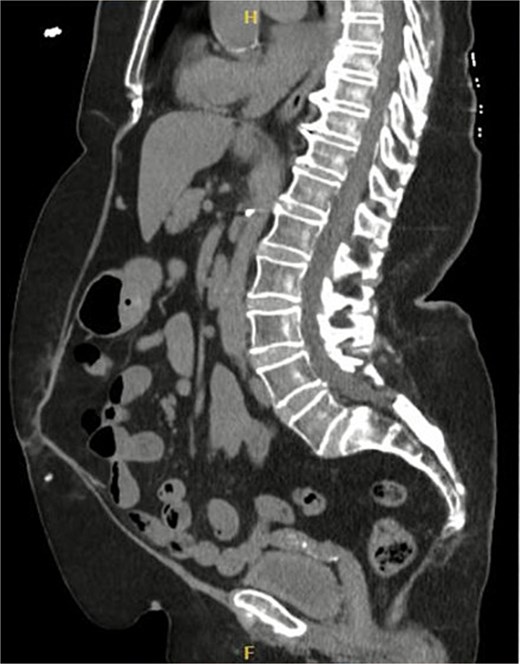

Sagittal section of CT abdomen and pelvis showing the ventral hernia.

Postoperatively, the patient had an uneventful course and was discharged on Day 5. At the 6-month follow-up, she remained asymptomatic. A CT scan performed at her request for reassurance showed no signs of recurrence or acute abdominal pathology (Figs 4 and 5).

Sagittal section of CT abdomen and pelvis 6 months after the surgery.